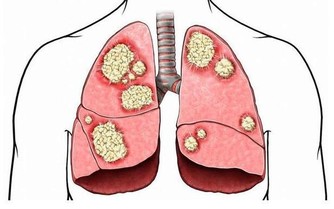

人體內的血液垃圾一般指體內物質的代謝產物,比如肝臟、腎臟、皮膚、肺臟等代謝產物。

人體各部細胞需要的氧氣和營養靠血液輸送,代謝過程中產生的廢物靠血液循環去排除。

而血液的任何病理變化都可能致病。佔人體體重8%左右的血液在維持生命活動中起著不可替代的作用。